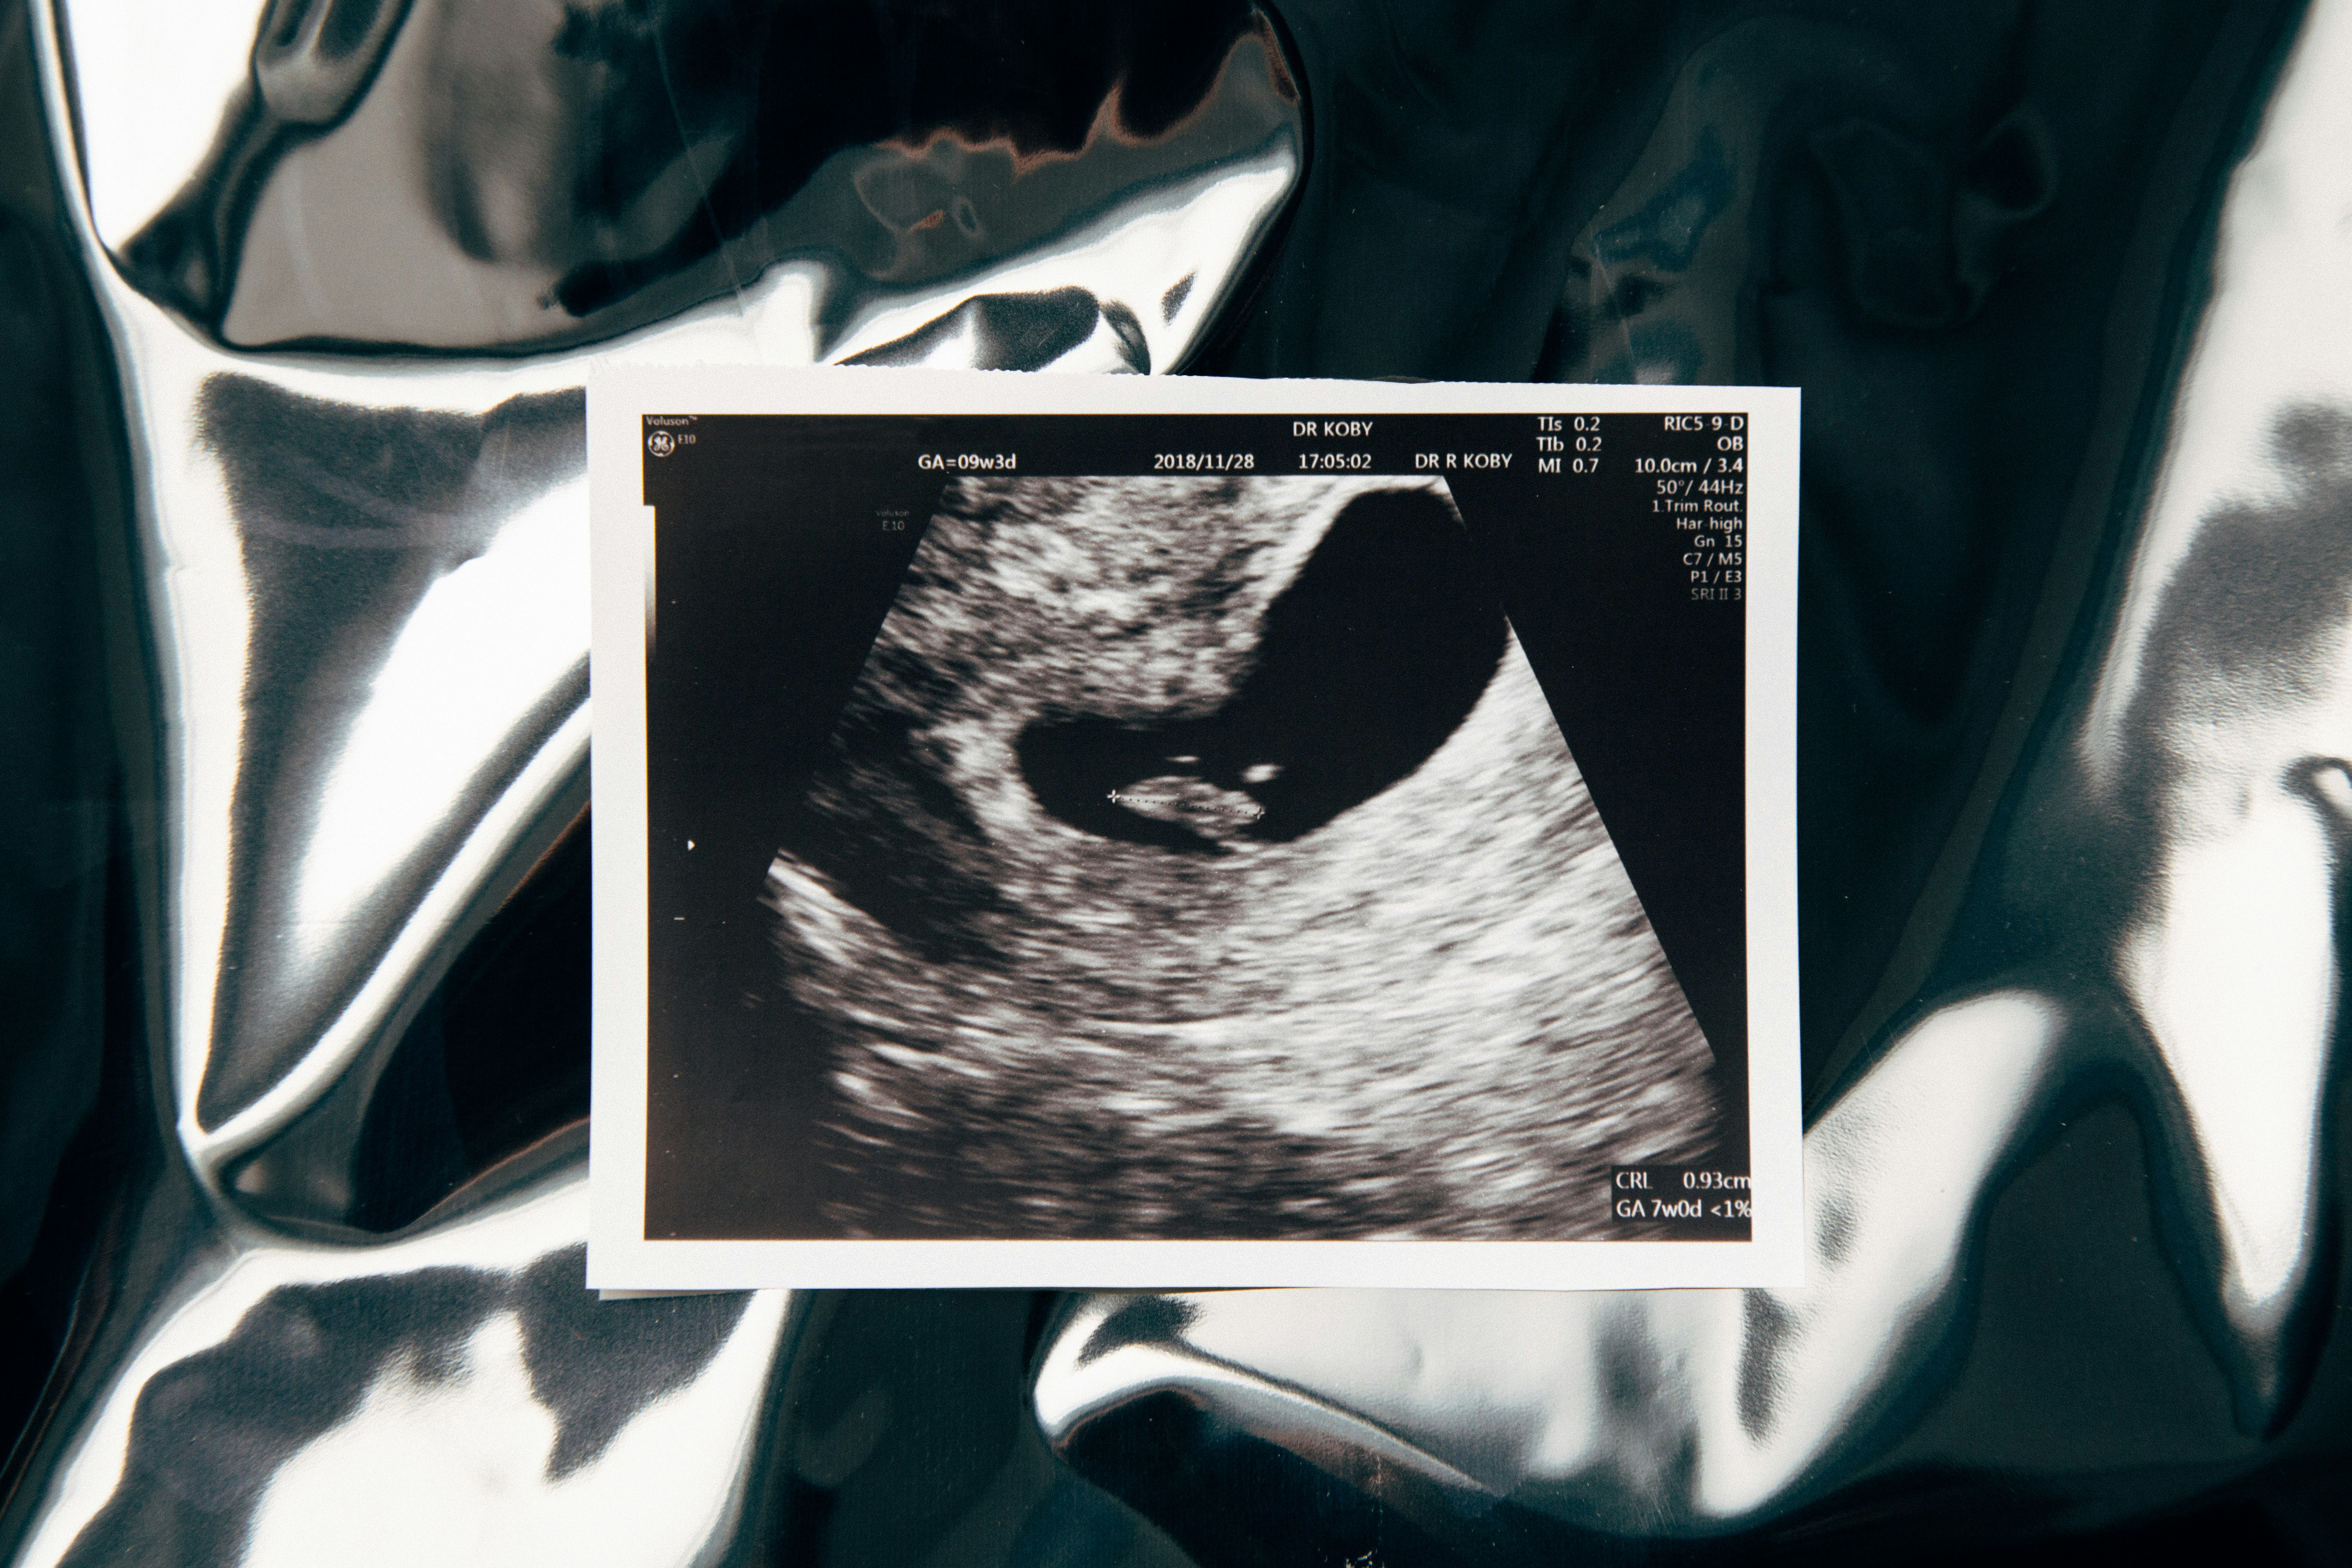

Ultrasound Imaging

Our ultrasound imaging offers clear, safe scans to help monitor your health and your family's well-being. Whether for pregnancy or general diagnostics, we provide quick, comfortable appointments with caring staff.